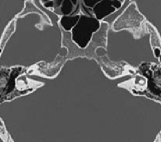

Annotation of the lateral semicircular canal plays an important role in the automatic calibration method of the raw temporal bone CT image. However, large-scale medical image data annotation is expensive and difficult to obtain. Therefore, we proposed an LSC segmentation algorithm to roughly predict the location of anchors. The lateral semicircular canal is a small sophisticated anatomical structure in the temporal bone. It is a semicircle canal that embedded in the temporal bone. In a CT volume, a lateral semicircular canal contains about 200 to 300 voxels. In different observation positions, the LSC vary greatly, as shown in Figure 2, which also makes it difficult to segment accurately.

Refer to caption

(a) Transverse position

(b) Coronal position

(c) Sagittal position

Figure 2: The LSCs in different views.